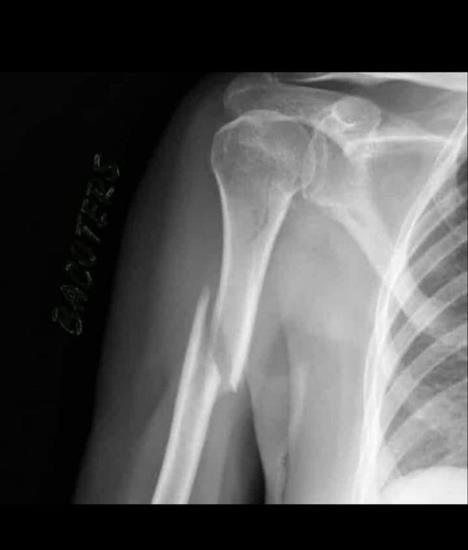

Naime, motor je udario Markeza i tom prilikom mu polomio nadlakticu. Nije dugo prošlo, a njegov snimak sa rendgena je procueo u javnost.

Specijalista traumatologije koji radi u Moto GP doktor Mir je rekao da mu pad nije polomio kost, već se to desilo kada se sudario sa motorom.

- Mark Markez je pretrpeo povredu od direktnog udara gume u desnu ruku, to je dovelo do frakture. Iako nije potpuno dislocirana, postoji mogućnost da ima paralizu radijalnog nerva, iako to nije sigurno. Odmah je imobilisan i prebačen u Barselonu na dalje lečenje - rekao je doktor Mir.

Ispostavilo se da je to operacija koja je vratila kost na mesto i tako može da se nastavi sa ubrzanim oporavkom.